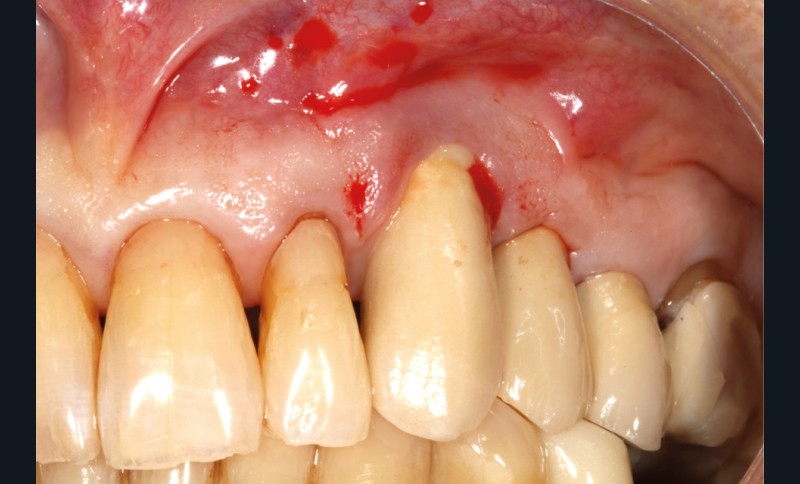

Le patient

- 70 ans

- Pas d’antécédents médicaux

- Ne fume pas

- Hygiène correcte

L’implant

- Site 23

- Mis en place il y a 12 ans